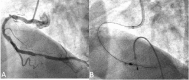

Figure 1

(A) A diagnostic image of right coronary artery (RCA) showing the previous stent with moderate stenosis in the distal part. (B) Insertion of a 5.5 Fr Guideliner catheter through the remaining rotablator system and retrieval of the entrapped 2.0 mm burr with success.